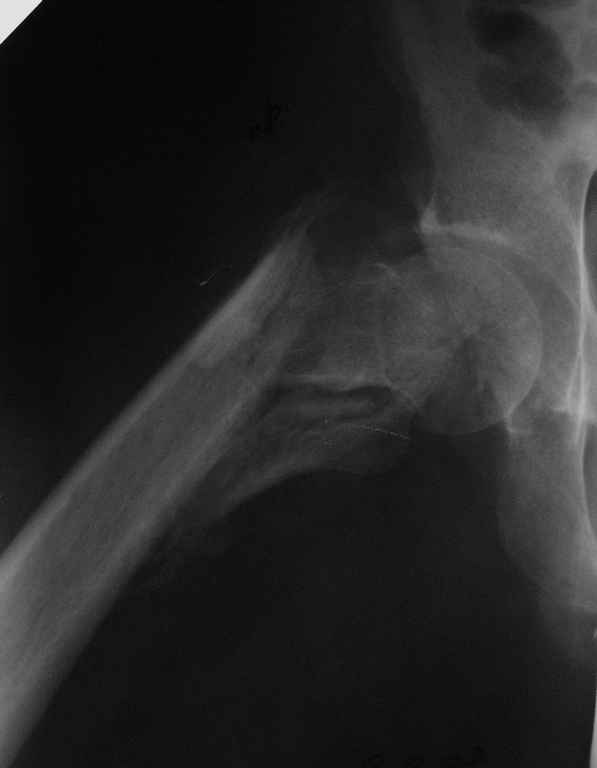

Пациент сорока лет с псевдартрозом правого бедра - исход оскольчатого чрезвертельного

перелома с отрывом большого и малого вертелов. Поступил через 8 месяцев после травмы.

По месту жительства лечили следующим образом: 2 месяца скелетное вытяжение, затем 2 месяца в

кокситной повязке. После снятия гипса дали нагрузку. В настоящий момент имеется укорочение

6 см. Патологическая подвижность. По данным КТ - сращения нет, имеется аваскулярный некроз

головки 2 стадии. В данном случае показано эндопротезирование тазобедренного сустава.